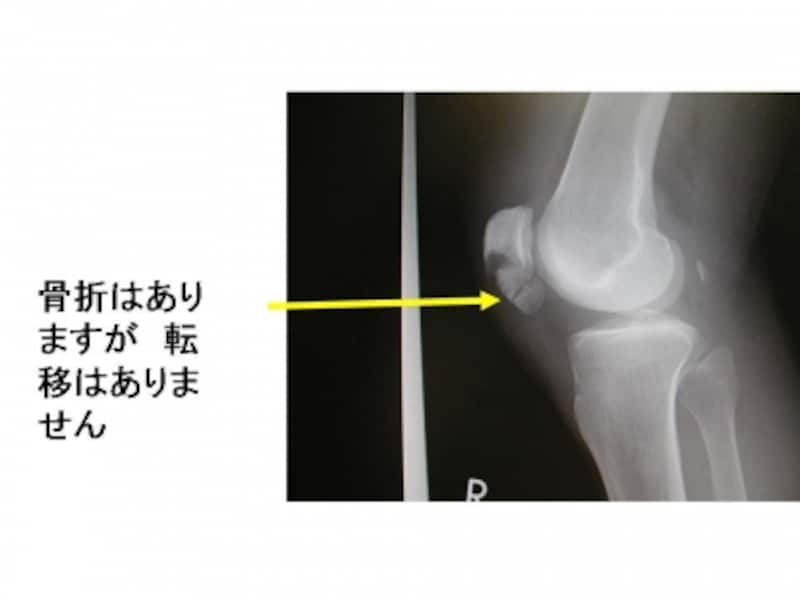

膝関節単純X線正面像。骨折した骨片が認められますが、あまりはっきりしません。

膝関節単純X線側面像。離断した骨片がよくわかります。

骨折した部位の腫脹と疼痛です。完全骨折では、強い疼痛、起立、膝関節の伸展が不能となります。転移がない場合、比較的鈍痛もしくは小さな痛みとなることが多く、見逃されることの多い骨折です。膝蓋骨骨折の診断

転移(骨のずれ)がない場合、保存的な治療が可能です。時間をかけて骨折した部位の骨癒合を計ります。長期間の固定が必要となりますので、運動、仕事の制限があります。